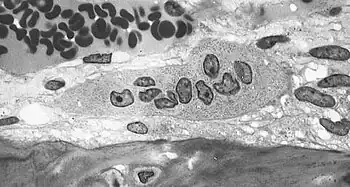

Osteoclast, with bone below it, showing typical distinguishing characteristics: a large cell with multiple nuclei and a "foamy" cytosol.